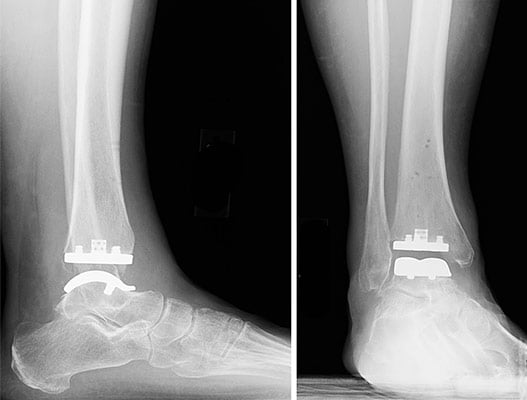

Lateral (side view) and anteroposterior (front view) X-rays showing the implants of a total ankle replacement.